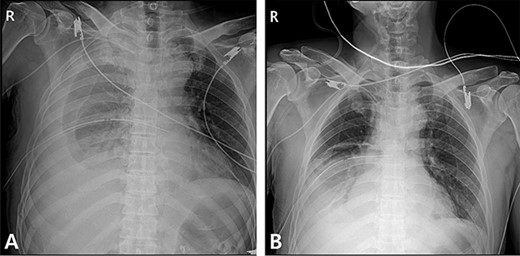

A 59-year-old man was admitted with multiple rib fractures and liver contusion due to a fall injury. He was standing on a chair for working at a farm, and it was knocked over causing him to fall and hit his flank against the corner of the chair. There was continuous pain while resting at the right flank and severe pain with pressure was noted, but no external wounds or bruises were observed. There were right 7th–11th rib fractures, scanty pneumothorax, minimal hemothorax and a 2-cm-sized liver contusion in abdomen and chest computed tomography (CT) scan (Fig. 1A, B). He was hospitalized for pain control and close observation in the general ward, and conservative management was initiated. Also, no significant changes were noted in the following daily follow-up chest radiographs. The patient suddenly complained of right-sided chest and back pain aggravation, cold sweating and fatigue 80 h after the traumatic injury. His mental status was alert, but v/s including systolic blood pressure (SBP) of 100–120 mmHg, heart rate (HR) of 40-60 beats/min and oxygen saturation of 100% during the admission changed to an SBP of 86/60 mmHg, HR of 88 beats/min and oxygen saturation of 97% when the symptoms occurred. Chest radiography was performed after the patient experienced aggravated symptoms, such as right-sided flank pain, cold sweating and fatigue. Compared to the previous scans, signs of increased opacification and peribronchial and parenchymal infiltrations were observed, which were indicative of hemothorax (Fig. 2A, B). We performed enhanced dynamic chest CT to identify any presence of active bleeding. On the chest CT scan, a large amount of hemothorax was identified in the right lung field along with multiple fractures of the right ribs. However, there were no signs of contrast leakage indicative of active bleeding (Fig. 3). Hemoglobin levels decreased from 13.1 g/dl on the day before the symptoms appeared to 11.5 g/dl at the onset of symptoms and to 9.4 g/dl after 2 h. Four packs of RBC transfusion and fluid were administered to the patient, and he was moved to the intensive care unit for close monitoring. And tube thoracostomy was performed, and 1600 ml of fresh blood was drained (Fig. 4A). The following day, 500 ml of blood was drained through the chest tube, but his v/s were stable (Fig. 4B). The amount of bleeding through the chest tube was decreased, but the drained fluid was fresh blood. And we thought that the remaining hematoma was not effectively drained, so the patient’s respiratory discomfort could persist and cause uneffective ventilation. And then we consulted with the Department of Thoracic Surgery, and video-assisted thoracoscopic surgery (VATS) exploratory thoracotomy was performed to identify the bleeding source caused by displaced rib and evacuate the large amount of hematoma. There was a large volume of hematoma within the pleural space and between the right lower lobe, diaphragm and fissure, but no active bleeding point was located. The fractured right 10th rib pierced through the pleural space and was displaced to the thoracic cavity, which was easily reduced. There was no injury surrounding the diaphragm, and although the general lung and chest wall contusions were severe, there were no signs of lung parenchymal lacerations (Fig. 5A–C). Chest tube drainage was serous, and there was no further bleeding. There were no signs of bleeding or any other abnormal findings on chest CT performed at the outpatient clinic, and the patient had no complaints of any symptoms (Fig. 6A, B).

Radiographic findings. (A) Day of symptoms, chest X-ray in the morning. (B) Chest X-ray after symptoms develop.